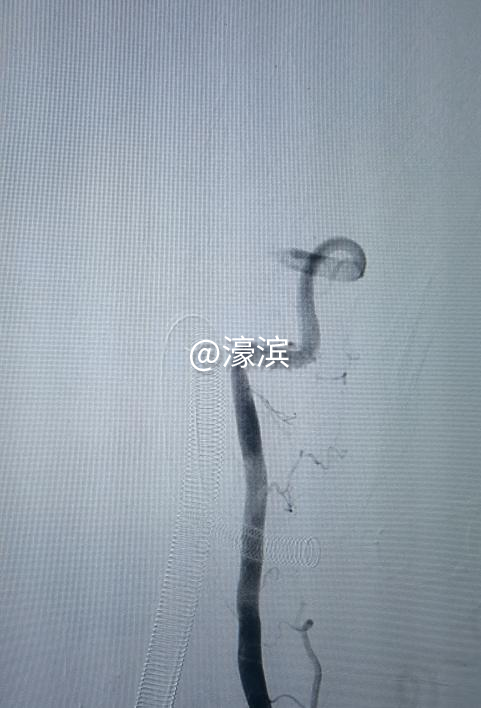

△张骐主任团队查看患者病情(中间:张骐) 突发脑梗危在旦夕 紧急救治抢抓“黄金时间” 57岁的肖先生因“发热3天,左上肢麻木伴头晕呕吐9小时”于2025年4月23日紧急入院。经检查,诊断为“急性基底动脉闭塞”,同时伴有高血压、血糖升高、冠状动脉粥样硬化性心脏病等基础疾病。头颅MRI显示基底动脉闭塞,两侧枕叶及延髓急性腔梗。基底动脉闭塞急性期的病死率为70%~90%,因此患者情况十分凶险。 “患者入院时已出现左侧肢体肌力下降、单眼视力模糊等症状,若不及时干预,可能导致永久性残疾或脑疝等致命并发症。”张骐主任表示。由于患者长期吸烟、饮酒,且未规律控制血压,血管条件较差,进一步增加了治疗难度。团队迅速启动卒中绿色通道,联合影像科、麻醉科、重症医学科等多学科专家会诊,在30分钟内完成术前评估,决定立即行“脑血管造影+经皮颅内动脉取栓术”。 多学科协作攻坚 微创技术打通“生命通道” 手术中,张骐主任团队行介入取栓技术,通过右侧股动脉穿刺,将8F Neuromax长鞘精准送至左侧椎动脉V1远端,利用6.3F抽吸导管对基底动脉闭塞段进行负压抽吸。经过两次抽吸,暗红色血栓被成功取出,血流恢复至mTICI 3级(最佳灌注),血管再通效果显著。

△取栓前后血管造影